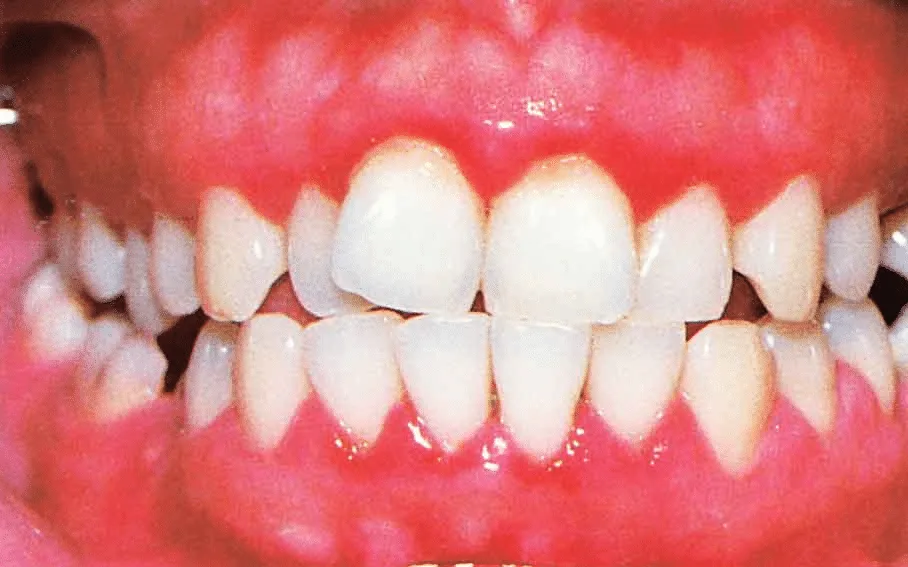

Hormone-Related Acute Gingivitis

Hormonal changes can affect gum health and increase the risk of gingivitis in two main ways: – By altering blood flow to the gum tissues – By interfering with the body’s ability to fight off toxins and bacteria associated with plaque and tartar buildupThis is commonly seen during puberty, pregnancy, and in women taking certain hormonal medications.